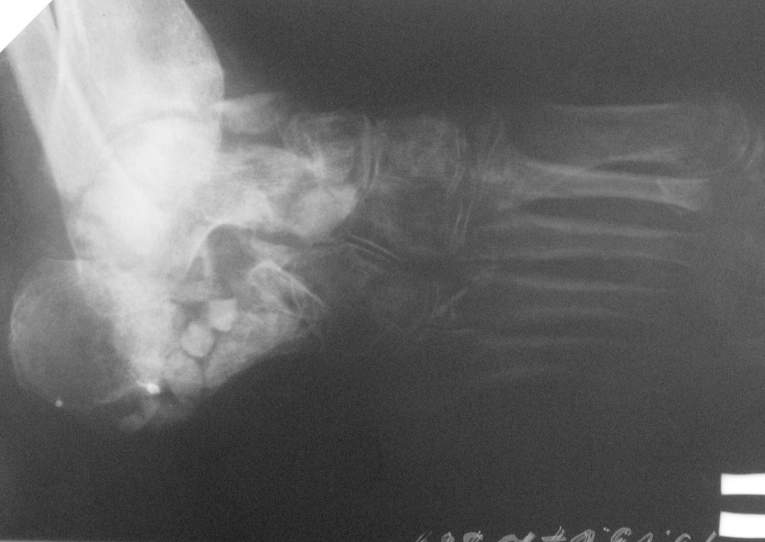

Re: Остеомиелит 4 плюсневой кости.

Спасибо за содействие )) В моем случае я не могу точно (без фистулографии, т.к. свищ закрыт) определить уровень и объем резекции кости в соответствии с будущей (надеюсь) операцией для восстановления опороспособности стопы. Или оставшихся трех лучей будет достаточно в ортопедической обуви? Предполагается резекция средней части диафиза 4 плюсневой кости с фистулонекрэктомией.

Не думаю, что потеря еще одного луча добавит опорности стопе. Как Вы планируете после резекции

восстанавливать длину плюсневой кости и добиваться сращения?

Предполагаемый общий (без деталей) план действий за 3тышшы км мне видится таким: 1.санация(нужна ли здесь резекция?),2. спейсер, 3.внешная или диафиксация. Можно добавить для стабильности и опорности на время лечения крепкую пластиковую лонгету на стопу. Кстати спейсер для костной полости не обязательно делать в виде бус.